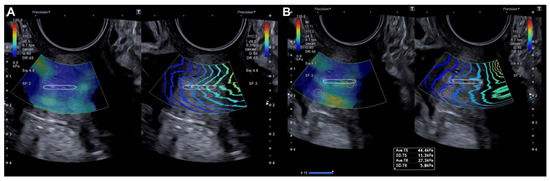

2.2.2. Evaluation Using SonoElastoColposcopy

- Sainz, J.A.; Castro, L.; Romo, J.M.; Holgado, A.; Fernández-Palacín, A.; García-Mejido, J.A. Evaluation of Pre-Malignant Lesions of the Uterine Cervix by Shear Wave Elastography: A New Diagnostic Tool. Ultrasound Med. Biol. 2021, 47, 3275–3282. [Google Scholar]

- Dudea-Simon, M.; Dudea, S.M.; Ciortea, R.; Malutan, A.; Mihu, D. Elastography of the uterine cervix in gynecology: Normal appearance, cervical intraepithelial neoplasia and cancer. A systematic review. Med. Ultrason. 2021, 23, 74–82. [Google Scholar] [CrossRef]

- Liu, C.; Li, T.T.; Hu, Z.; Li, Y.; Cheng, X.; Zhu, Y.; Lu, M. Transvaginal Real-Time Shear Wave Elastography in the Diagnosis of Cervical Disease. J. Ultrasound Med. 2019, 38, 3173–3181. [Google Scholar] [CrossRef]

| Exocervix (kPa) | 19.98 (±9.29) | 105.42 (±36.32) | p < 0.0001 |

| Endocervix (kPa) | 18.5 (±9.07) | 109.8 (±40.86) | p < 0.0001 |